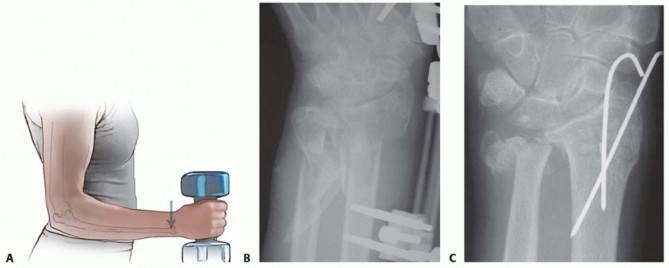

Closed Reduction and Percutaneous Pinning of Supracondylar Fractures of the Humerus